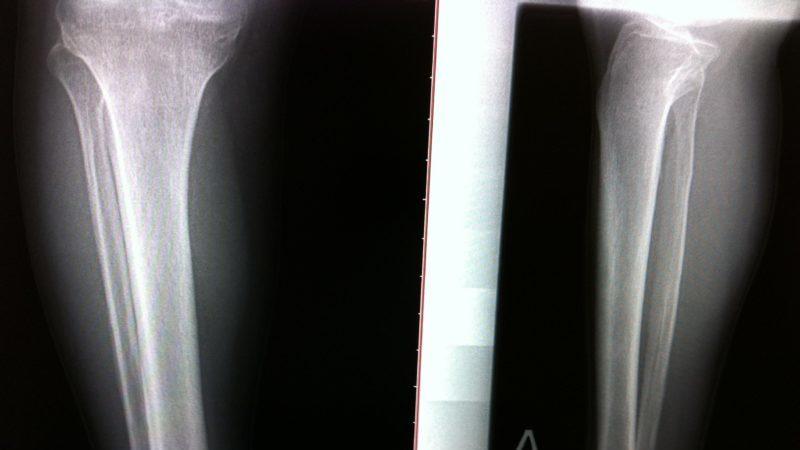

Фото болезни:

- рентгенографическое исследование голени;